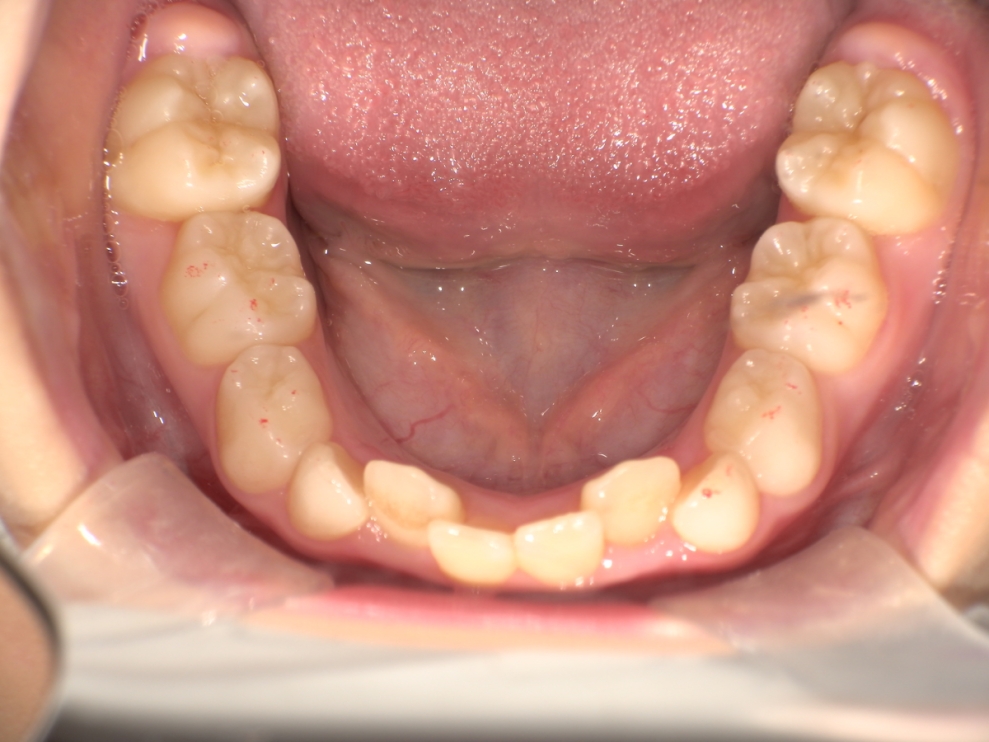

BEFORE

スタート時8歳の女の子の症例です。主訴は歯並びのガタつきでした。2年前に歯科医院で「顎が小さく、このままだと歯並びが悪くなる可能性がある」と指摘を受けていたことや、学校健診でチェックが入ったことをきっかけにご相談に来院されました。診査の結果、歯列のガタつきに加え、深い噛み合わせの状態も確認されました。

できるだけ痛みや不快感の少ない方法で治療を進めたいとのご希望があり、「しっかり治るのであれば期間にはこだわらない」と前向きなお気持ちで治療に臨まれました。